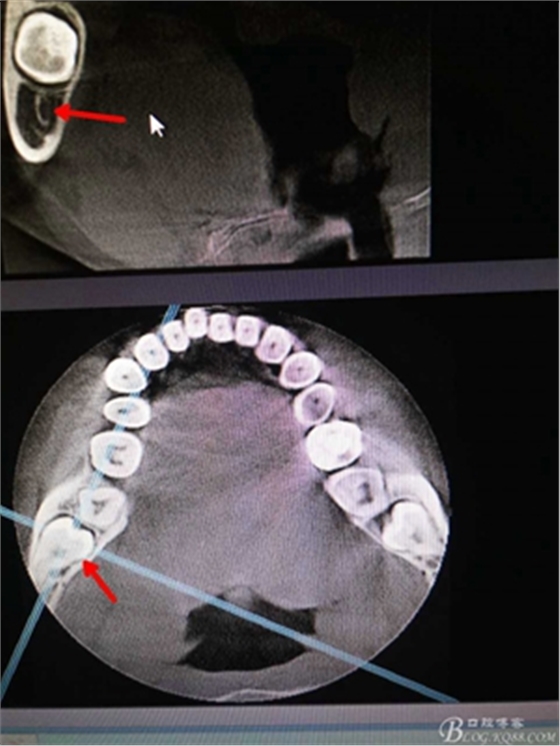

圖2.術(shù)前的cbct檢查:38牙冠周?chē)泄墙M織覆蓋,下頜神經(jīng)管離38牙冠還有一定距離,在去除牙冠的時(shí)候,損傷神經(jīng) 的風(fēng)險(xiǎn)較小。38牙根舌側(cè)骨壁較薄。

圖3.冠向檢查:38牙根未進(jìn)入下頜管內(nèi),牙冠周?chē)醒滥矣啊?p style="text-align:center">